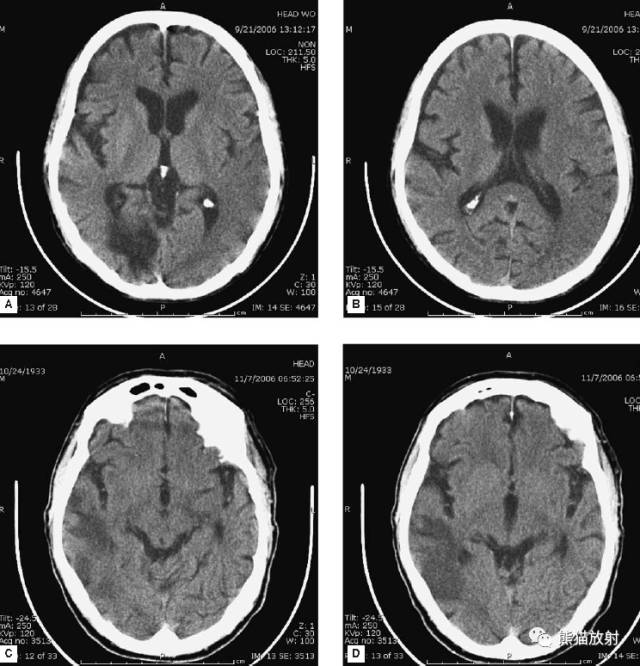

动脉瘤破裂导致蛛网膜下腔出血、脑室积血、非交通性脑积水。

与外伤性蛛网膜下腔出血不同,动脉瘤破裂导致的SAH常不累及大脑凸面,而位于基底池附近。脑动脉瘤常位于鞍上池的Willis环血管。

A:四脑室积血;B:中脑导水管、环池、右侧侧脑室颞角积血,前交通动脉处(动脉瘤好发位置)出血密度较高;C:三脑室积血;D-F:侧脑室积血,蛛网膜下腔出血(血液代替了脑脊液)。

5、高血压性脑出血

高血压性脑出血:

- 自发性出血;

- 继发于长期高血压及慢性血管病;

- 常见于基底节区、丘脑、脑桥、小脑。

A:占位效应,相邻脑沟、脑池消失;F:脑出血破入四脑室。

钩回疝:是当代偿机制不能适应占位性病变时的结果。

基底节区大量高血压性脑出血,破入脑室及蛛网膜下腔,周围水肿,脑干周围空间消失;脑干出血、脑积水。